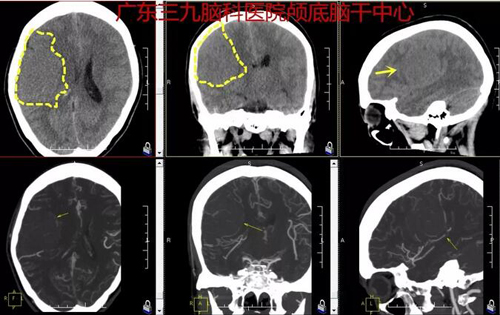

今年8月初,邱女士因“间断头痛1年余,伴加重1年余”来神经外一科门诊就诊,经检查,影像结果示:右侧额颞顶部占位性病变。张良主任医师介绍,从影像资料中可以看到患者脑中的肿瘤体积为5.6cm×4.8cm×5.6cm,有鸡蛋大小。经充分术前讨论,考虑术中可能出现的各种情况,制定了详细的手术方案。4天后行“右侧额颞顶部占位性病变切除术”,术程顺利,术后病理报告示:非典型脑膜瘤。

图1:术前CT及CTA结果示右侧额颞顶部颅骨内板下示一类圆形占位性病变,其内及边缘有少许小血管影,右侧大脑中动脉及其分支受压内移,中线结构稍偏左。

图2:术前MR检查示右侧额颞顶部占位病变,范围大小约5.6cm×4.8cm×5.6cm,术后MR报告示:右侧额颞顶部占位性病变切除术后呈术后改变,原病变已切除。